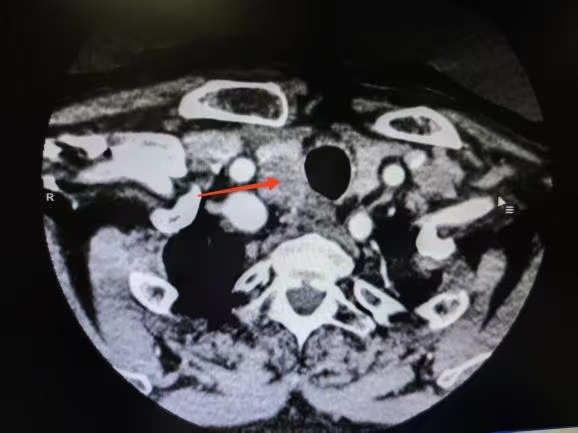

CT箭頭所示:右側(cè)甲狀腺腫瘤

荊楚網(wǎng)(湖北日?qǐng)?bào)網(wǎng))訊(通訊員 楊青青 沈浩元 )近日,孝感市中心醫(yī)院甲狀腺乳腺外科成功為一名67歲男性患者實(shí)施了高難度甲狀腺癌根治手術(shù)。該患者因頸部突發(fā)硬塊4天就診,經(jīng)檢查確診為雙側(cè)甲狀腺乳頭狀癌伴右頸側(cè)區(qū)多發(fā)淋巴結(jié)轉(zhuǎn)移,術(shù)中進(jìn)一步發(fā)現(xiàn)腫瘤已侵犯包繞喉返神經(jīng),側(cè)區(qū)轉(zhuǎn)移淋巴結(jié)亦侵犯頸內(nèi)靜脈,病情復(fù)雜且兇險(xiǎn)。